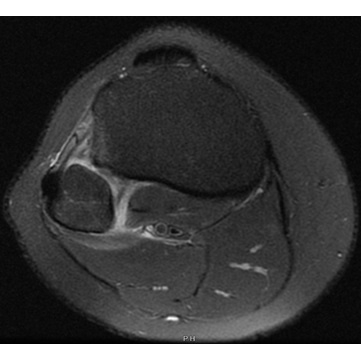

Independent interpretation of knee radiographs obtained at initial presentation in the ED were concerning for possible subluxation of the fibular head, with no acute fracture noted. Given the concern for high ankle sprain, radiographs of the right ankle with stress views were obtained in clinic which demonstrated a congruent ankle mortise with no acute fracture or evidence of instability on stress views Case Photo #5 . In addition, an MRI of the right knee without contrast was obtained which demonstrated full thickness tearing of the posterior tibiofibular ligament from its fibular attachment, partial tearing of anterior tibiofibular ligament, a small effusion of the proximal tibiofibular joint, and slight subluxation of the fibular head consistent with tibiofibular joint instability, with no fracture or chondral injury Case Photo #6 [Photo7].